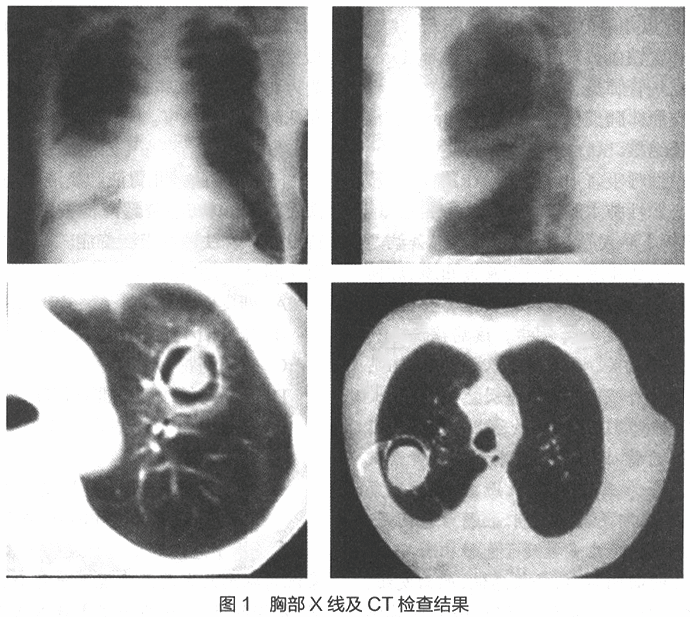

患儿男性,12岁,近1周来发热,伴咳嗽。患儿为白血病(急淋)缓解期,长期服用激素,查体:体温38℃,面色可,周围循环好,心脏(-),右肺可闻少许湿啰音,腹(-),下肢无水肿,神经系统检查(-)。胸部X线及CT检查如图1。

(1). 与该病例影像学检查改变相符的疾病是